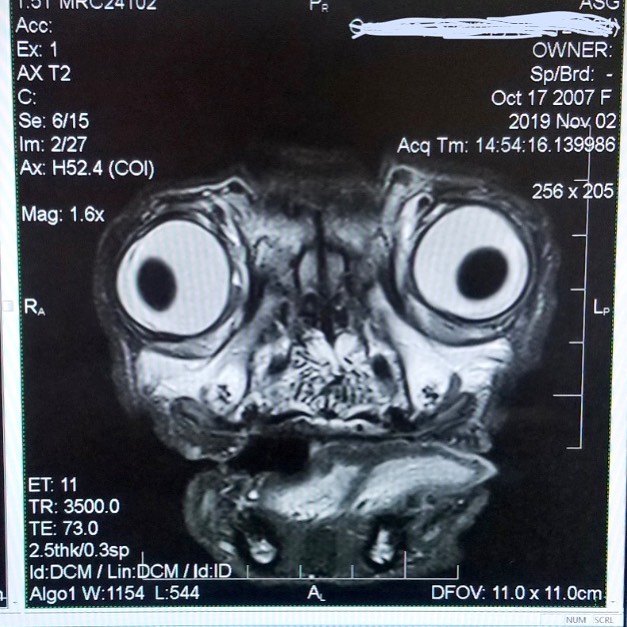

Рентгеновский снимок мопса напугал соцсети

Рентгеновский снимок сделал мопса звездой интернета. Фотографию опубликовал телеведущий Энди Ричтер. Пес принадлежит его другу. На снимке мопс больше похож на чудовище с выпученными глазами. Пользователи в комментариях стали писать, что фото настолько ужасно, что теперь они могут заснуть.

Также многие стали спрашивать, а все ли в порядке с собакой. Но Ричтер заверил, что у мопса все хорошо, и выложил новое фото, где собака греется на солнце.